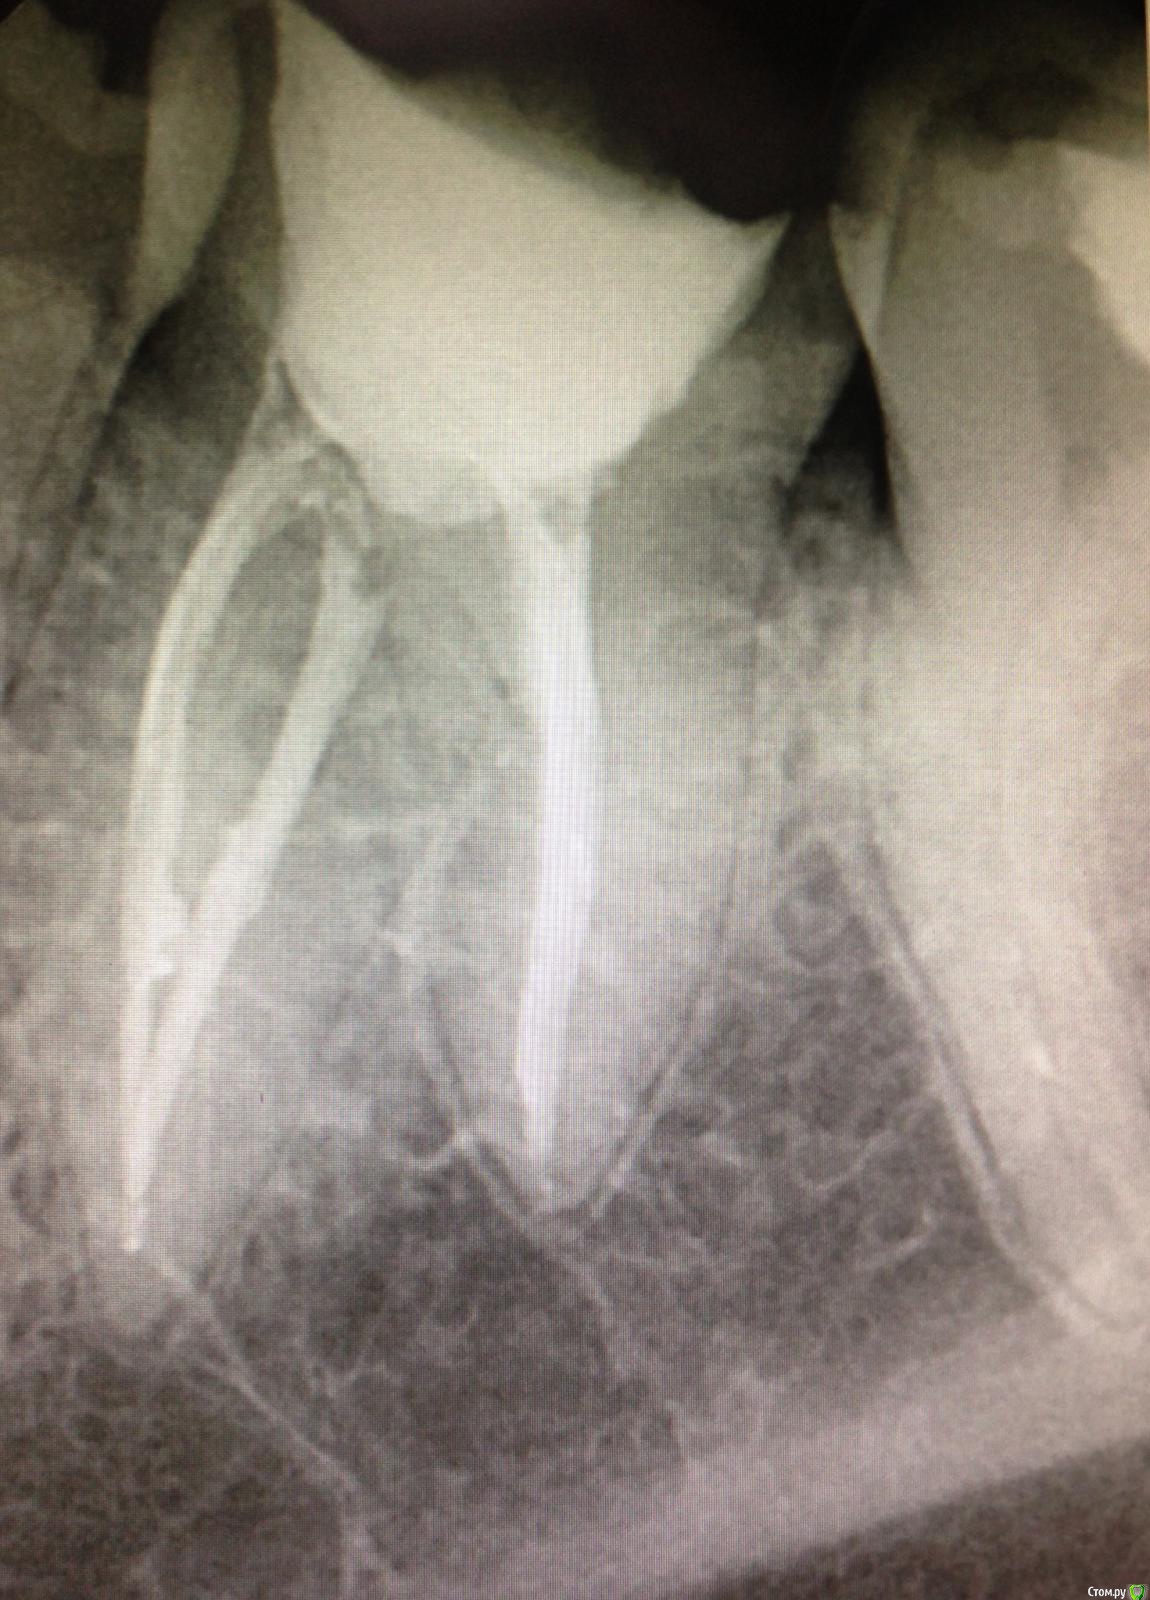

SSTi Опубликовано 12 декабря, 2014 Автор Поделиться Опубликовано 12 декабря, 2014 Еще 1 пульпитный красавчик Ссылка на комментарий